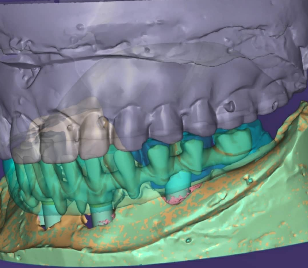

Prótesis fija

Estructuras, híbridos y soluciones estéticas con control digital y acabado de precisión.

Estructuras, híbridos y soluciones estéticas con control digital y acabado de precisión.

Estructuras metálicas de alta precisión, ajuste estable y diseño funcional adaptado a cada caso clínico.

Diseño 3D, planificación y fabricación controlada. Optimizamos tiempos y mantenemos consistencia en cada fase para reducir sorpresas en clínica.